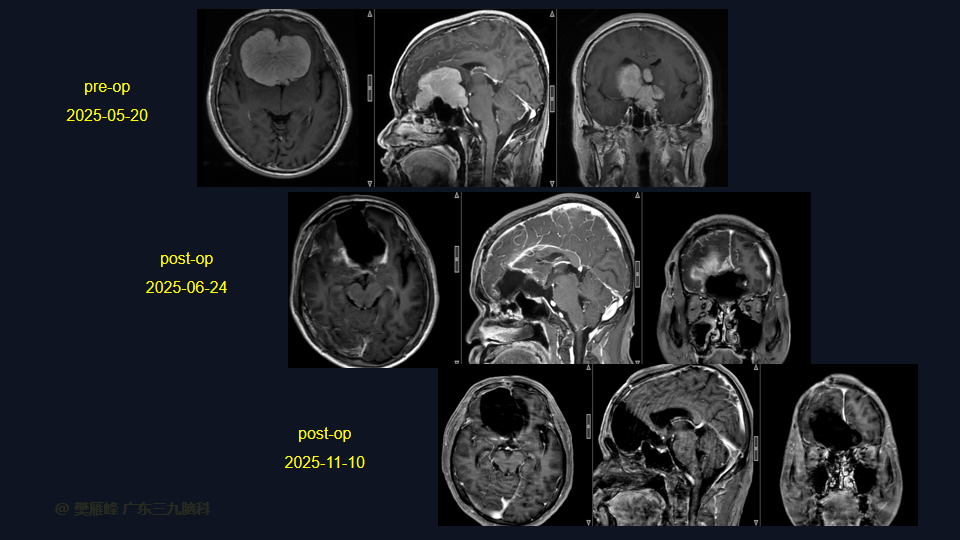

在这个二维手术视频中,展示了一种经前纵裂额底入路切除巨大嗅沟脑膜瘤的方法。患者是一名52岁的男性,有双眼视物模糊3月、无步态不平衡病史,神经影像学显示前颅窝、双侧鞍旁、桥前池示一巨大团块状等T1长T2,FLAIR序列高信号,明显强化,其内示多发流空信号影,邻近双侧颈内动脉及双侧大脑前动脉被包绕,大小约77×62×51mm的嗅沟脑膜瘤。术中实现肿瘤全切除。术后3月双侧嗅觉基本同术前,双侧视力较术前好转,神经影像学显示肿瘤全切。我们展示了安全的颅神经和肿瘤切除术的细微差别和技术要点,包括:采用降低硬膜开口的颅底法,保留额叶静脉,防止静脉损伤。诊断时,尽管患者嗅觉常常缺失,但仍有至少保留一根嗅觉通路。通过精准的解剖重视A2段的保护。最后,需要多层重建颅底。